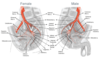

Arteries of Pelvis

Branches off Common Iliac a.

Female and Male Pelvic A.

Uterine & Vaginal A.